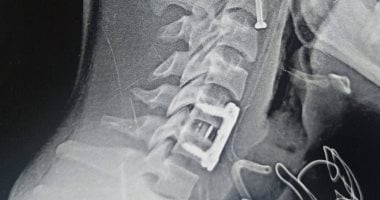

نجح فريق جراحي بقسم جراحة المخ والأعصاب بمستشفي بنها الجامعي بمحافظة القليوبية، في إجراء عملية جراحية معقدة وفريدة من نوعها، لإنقاذ مريض عانى من كسور خطيرة في الفقرات العنقية كادت أن تودي بحياته أو تتسبب في إعاقة دائمة "الشلل" بعد سقوطه من علو. وأوضحت مستشفيات بنها الجامعية، في بيان لها، أنه جاءت ا...